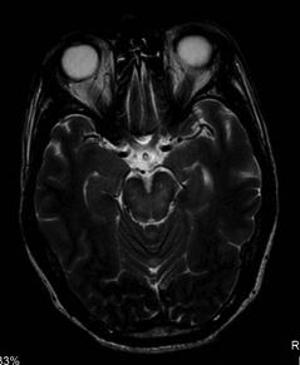

Another study analyzed the imaging results of three target groups affected by Zika: adults who developed acute neurological syndrome, newborns with vertical infection with neurological disorders, and pregnant women with rash outbreaks suggestive of Zika.

Many of the adults had symptoms of Guillain-Barré syndrome, a rare disorder in which the body's immune system attacks the nervous system causing rapid onset muscle weakness. A few showed inflammation of the brain and spinal cord (Bickerstaff's encephalitis) or brain stem and spinal cord lesions. Common MRI findings included enhancement of certain spinal and facial nerves. In the newborns, MRI showed orbital injuries and anatomical changes in brain tissue.

"It was alarming to find so many cases of neurological syndromes in adults, some very serious, related to Zika virus infection," said study author Emerson de Melo Casagrande, M.D., from the Department of Radiology at Antonio Pedro University Hospital - Federal Fluminense University. "We have also noticed a difference between these syndromes, even though the trigger was the same."